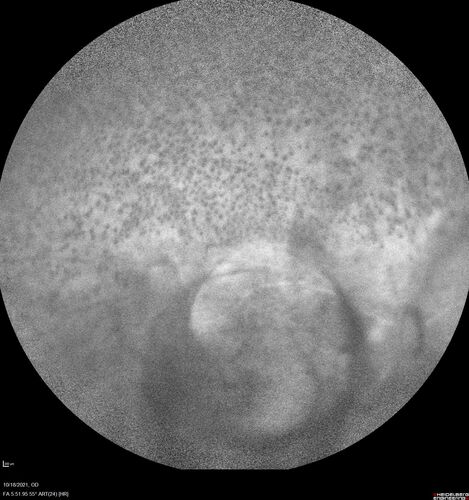

Severe Syphilitic Placoid Chorioretinitis

68 year old man 3 months ago the vision started fading in both eyes.  Just sitting here he can see some light out of his right eye. The patient denies any recent illness or travel.

VA: OD: LP, OS: 4/200

IOP: 9, 13

Anterior segment: 1+ cell/ 2+ flare OU and 2+ NS and anterior vitreous cells

Labs Reactive RPR 1:256, FTA-ABS - reactive - Patient was admitted to hospital for IV PCN and recovered vision almost completely in the left eye and some in the right eye.